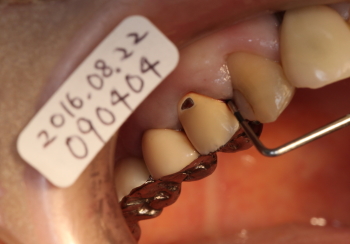

ポケット測定

短針を挿入した像

かなり深い